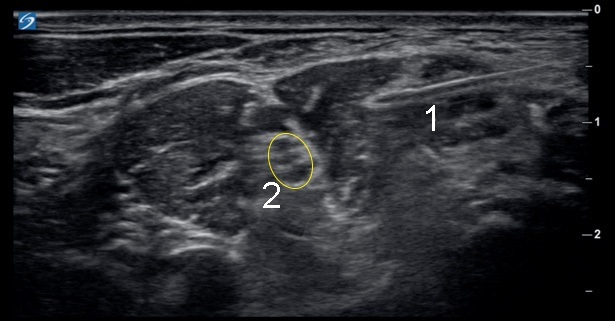

Interscalene Nerve Block - Needle Insertion Image

Needle

Brachial Plexus